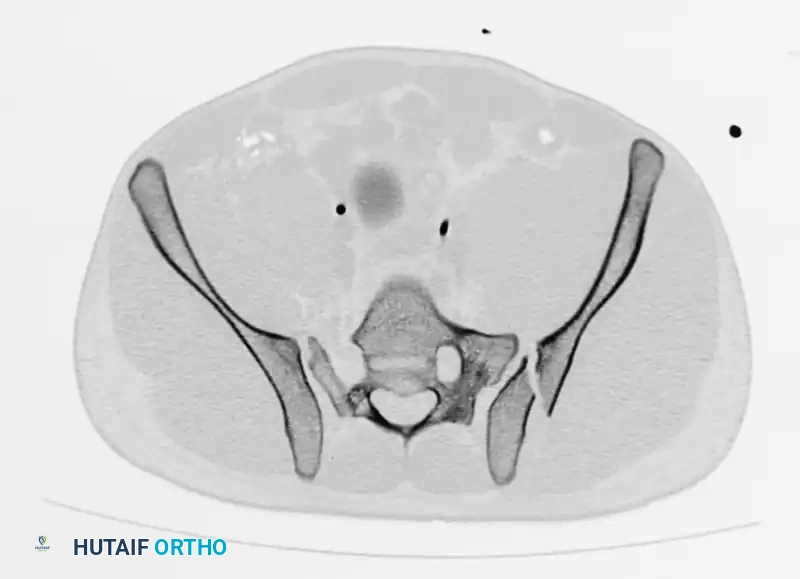

Axial CT imaging confirms the complete dissociation of the sacroiliac articulation, highlighting the profound instability of the posterior tension band.

FIGURE 56-45: Young and Burgess anteroposterior type III (AP III) pelvic ring injury with pubic diastasis and bilateral pubic rami fractures. A-C, Preoperative anteroposterior, inlet, and outlet views, respectively. D, Preoperative CT scan.

Surgical Management:

AP III injuries require robust anterior and posterior fixation. Anteriorly, a symphyseal plate or external fixator is applied. Posteriorly, percutaneous iliosacral screws (placed into the S1 and/or S2 vertebral bodies) or posterior tension band plating is required to counteract vertical shear forces and allow for early mobilization.